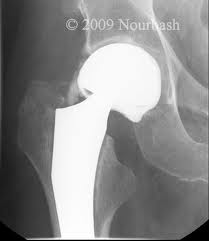

Hip replacement loosening occurs over time, and can cause problems with the normal function of the hip replacement prosthesis. When a hip replacement is placed into the body, it is either press-fit into the bone, or cemented into position. Either way, it is fit tightly into the bone of the thigh (femur) and pelvis so that the implant cannot move. When implants loosen, the hip replacement can begin to move small amounts. Usually this is associated with increasing pain and loss of motion experienced by the patient.

Osteolysis is a problem that causes the bone surrounding the implant to seemingly ‘melt away’. The weakening of bone around the hip replacement is seen on x-rays, and looks as though there are holes in the bone around the joint replacement. Because of the weakened bone, the hip replacement become loose, and begins to wobble within the bone. Patients experience symptoms of pain and limitations in motion of the hip. The technical name for this weakening of bone is called osteolysis.